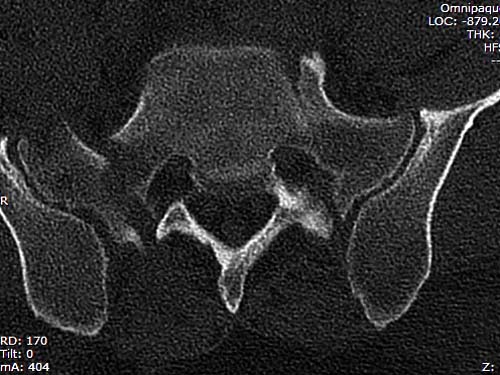

Двухстороннее повреждение крестца и травматическая ампутация бедра, где

неопытной бригадой дежурантов установлен верхний наружный фиксатор для

стабилизации. На третий день ревизия на более стабильный, и

окончательная фиксация. Первые снимки после стабилизации таза, и другие,

где показаны (параллельные) правильная установка на AIIS т.е на месте

прикрепления прямой мышцы бедра. Ампутация закончена костно пластическим

методом.